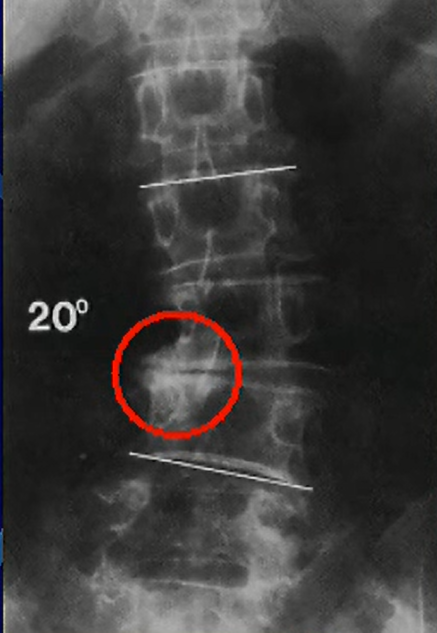

右の画像は変性側弯症のレントゲン写真です。

これは正面から見ている画像です。

右の椎間板が低くなったせいで上下の椎体辺縁がぶつかり骨棘が形成されているのが分かります。

そして神経根を圧迫するのでラディキュロパシーを生じます。